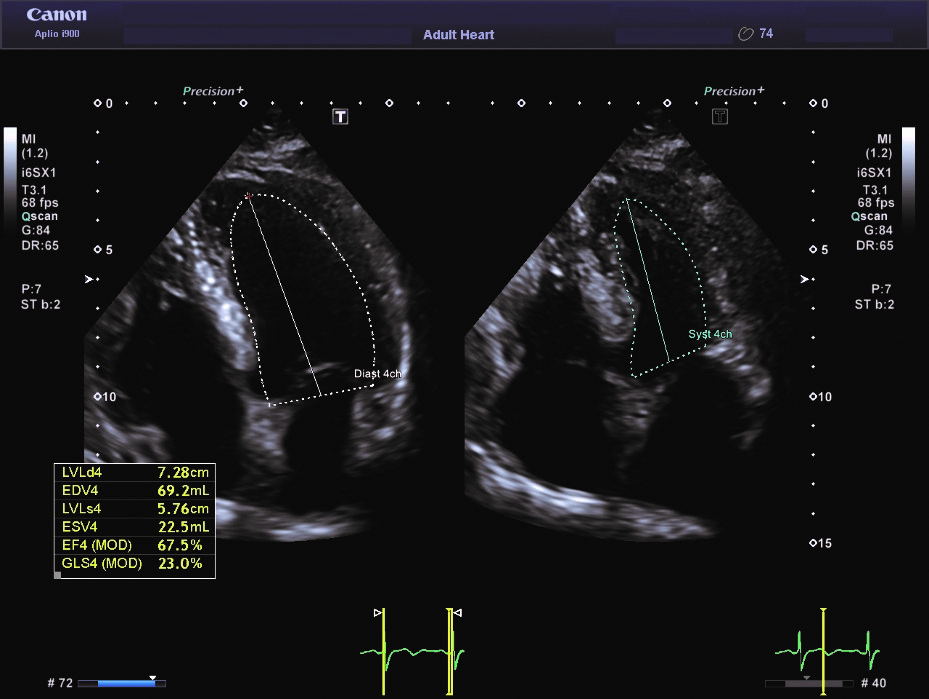

Мал. 1. Авто ФВ у апікальному 4-камерному зображенні легко оцінює функцію ЛШ з мінімальною необхідністю коригування трасування

Повністю автоматизоване вимірювання ФВ може бути виконано за лічені секунди, це технічно можливо та співставно з ручним трасуванням у 2D спекл-трекінгу4,5. Крім того, Авто ФВ є більш достовірною, ніж візуальна оцінка «на око», виконана навіть досвідченим фахівцем5. Такий автоматизований аналіз також надає інформацію (прорахування об’ємів ЛШ і ФВ, включно з глобальним поздовжним стрейном(GLS), яка, на відміну від традиційних методів оцінки ФВ і GLS, не має варіабельності4.